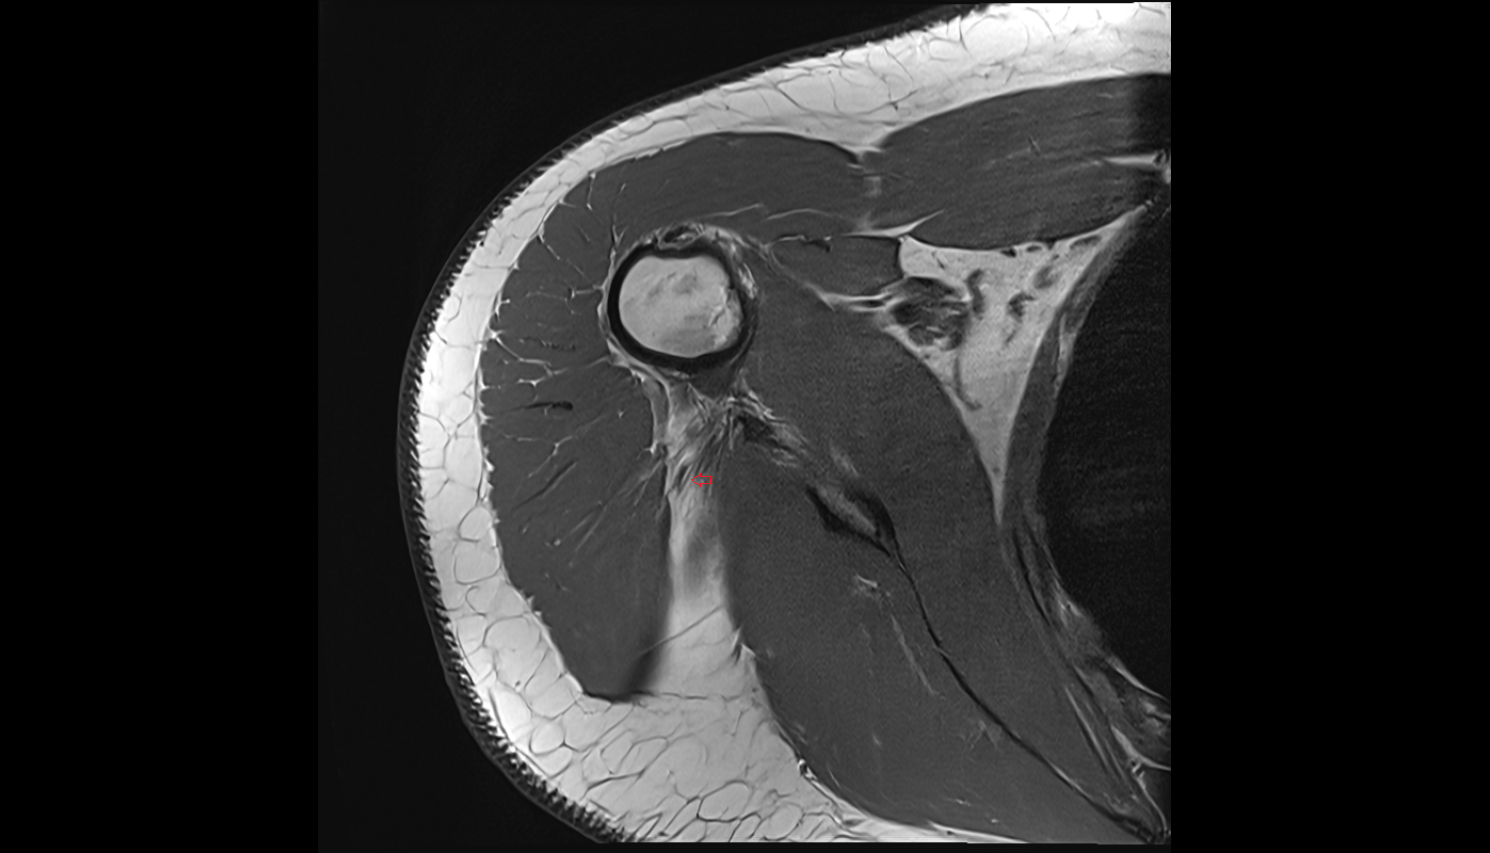

- Shoulder joint (glenohumeral joint)